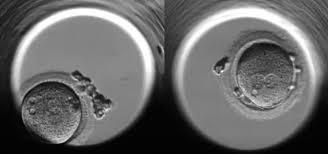

النطفه قال تعالى: {أَلَمْ يَكُ نُطْفَةً مِنْ مَنِيٍّ يُمْنَى} [القيامة:37].

العلقه قال تعالى: {ثُمَّ كَانَ عَلَقَةً فَخَلَقَ فَسَوَّى} [القيامة:38]